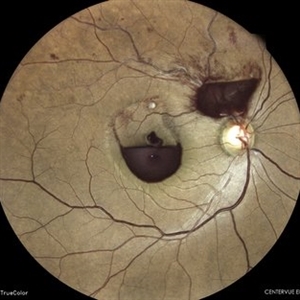

Old Supero-Temporal Branch Retinal Vein Occlusion with Macular Hole Right Eye Fundus

Fundus photograph of a 36-year-old female presented with supero-temporal branch retinal vein occlusion with macular hole in right eye.

Photographer: Dr. Akansha Sharma-Retina Foundation

Condition/keywords: branch retinal vein occlusion (BRVO), macular hole